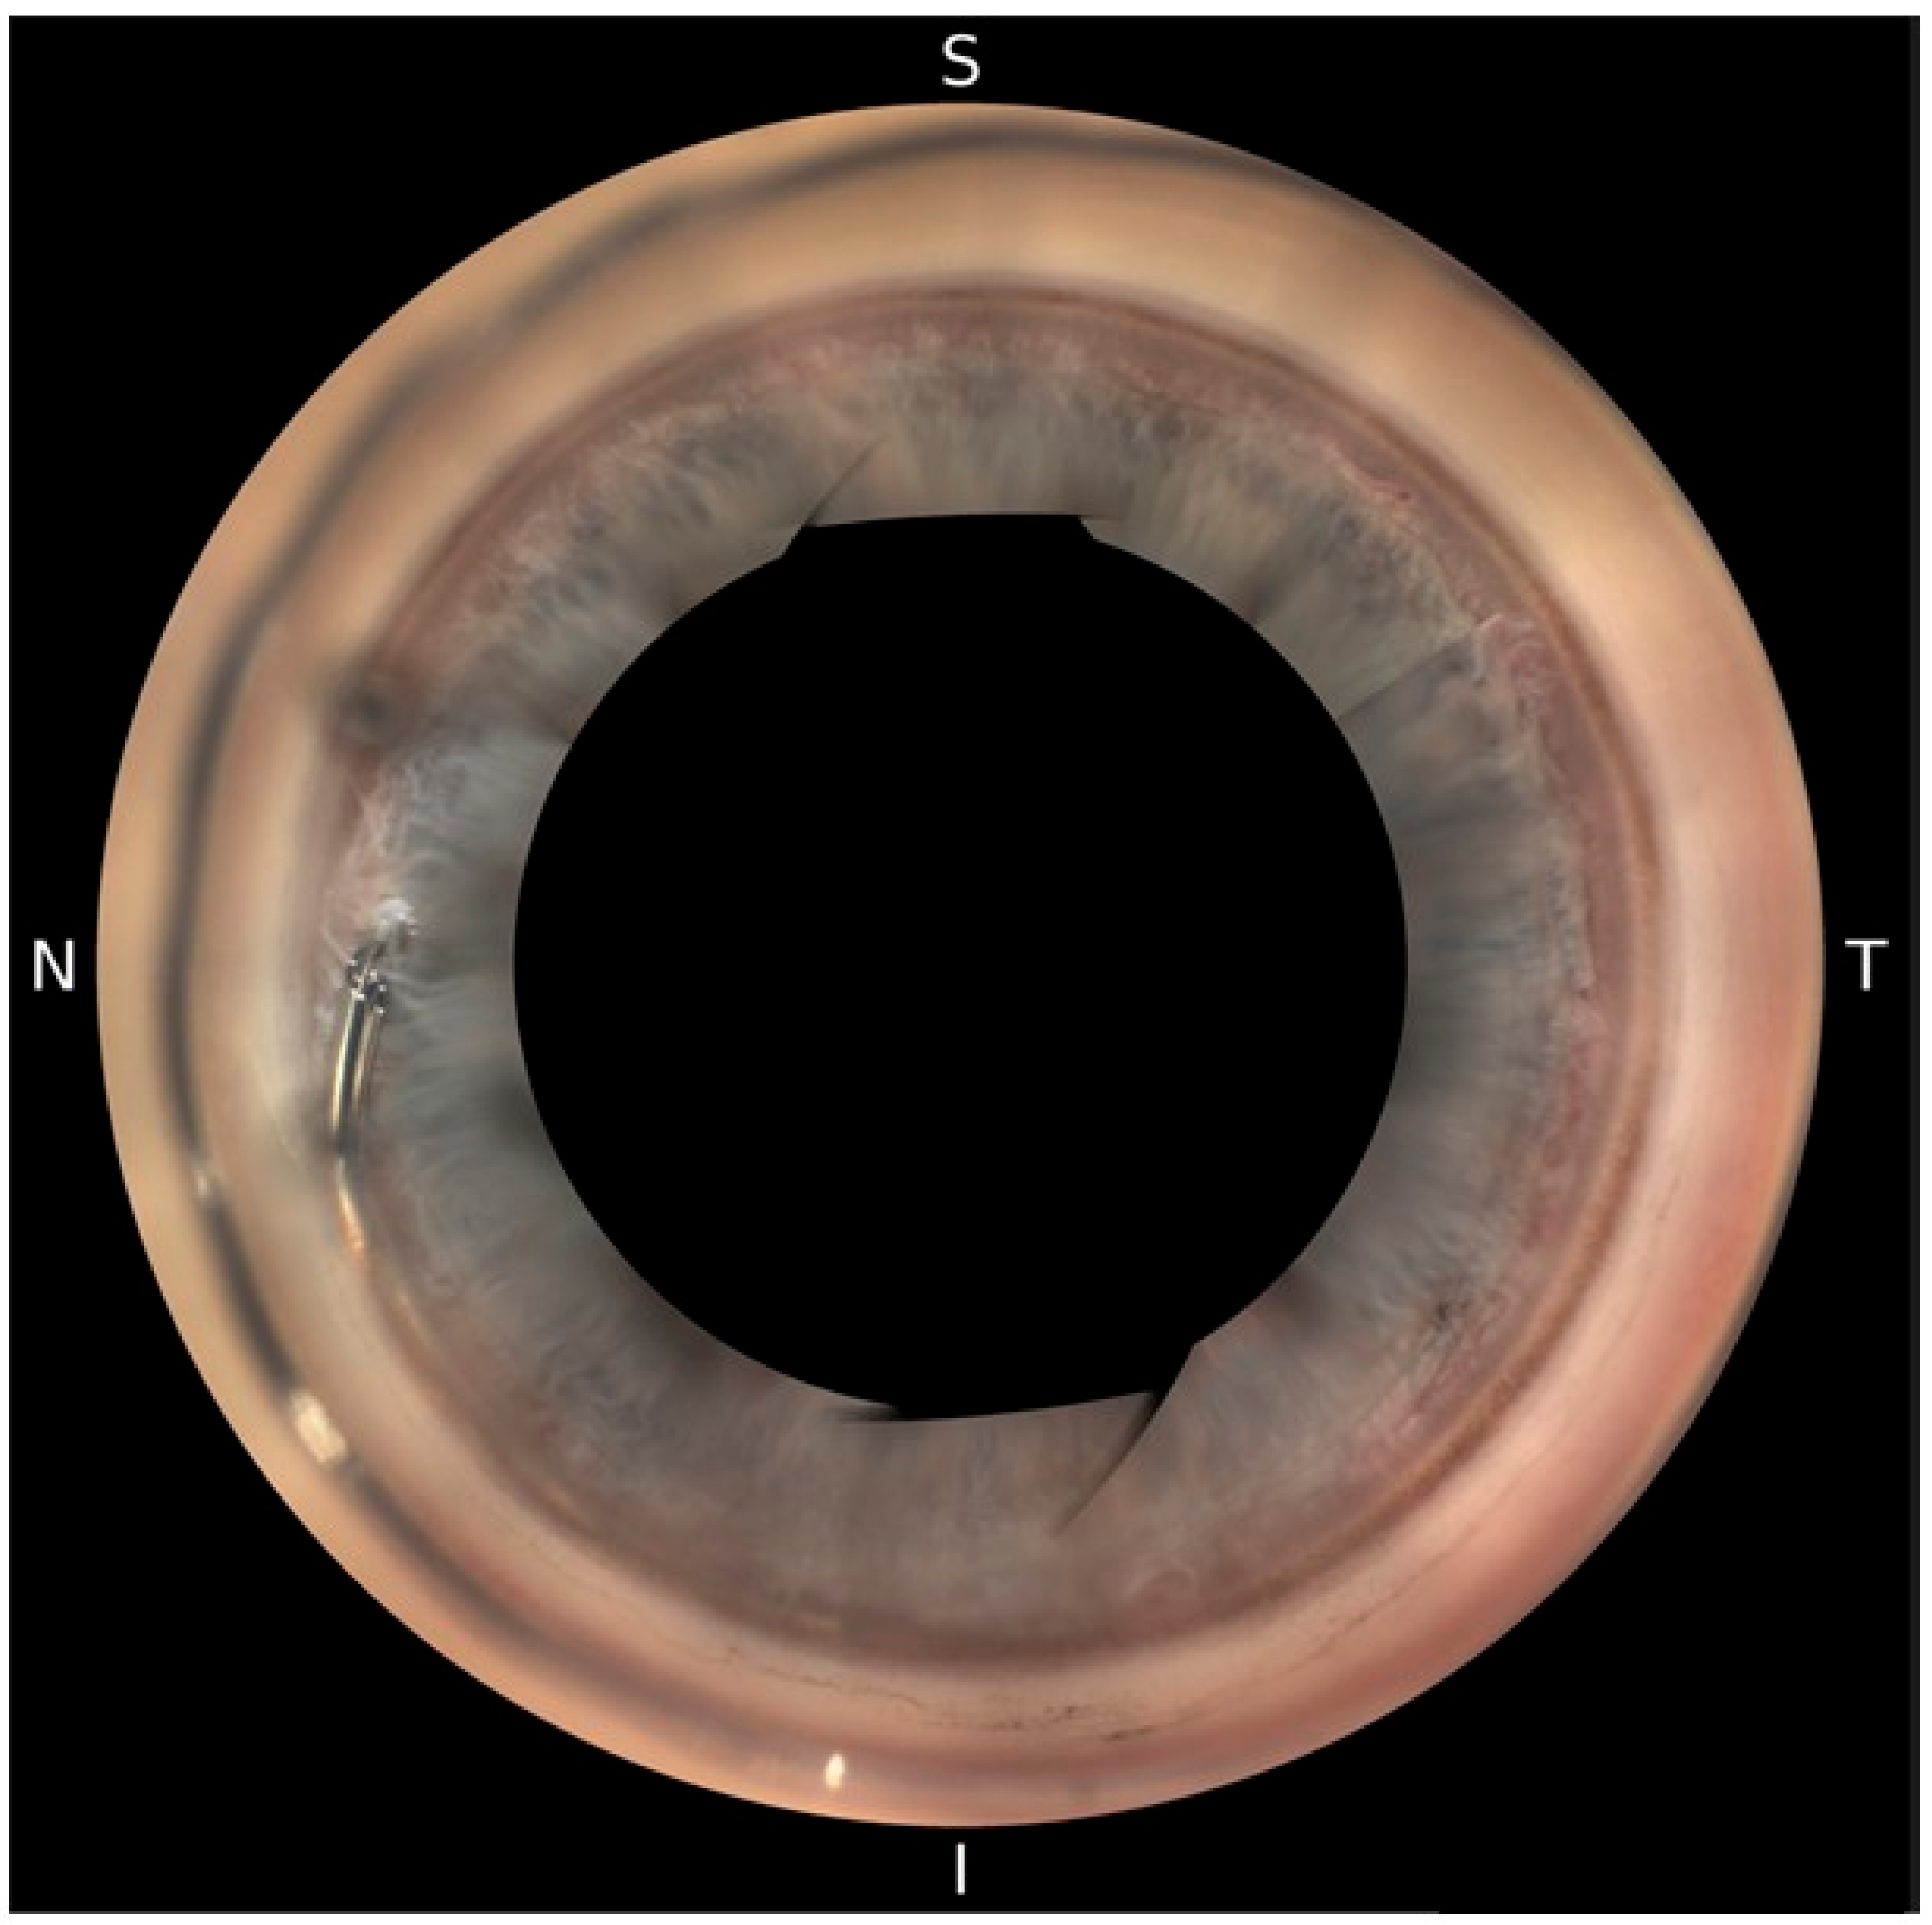

Postoperatively, patients underwent automated 360° gonioscopy to visualize the postoperative positioning of the Hydrus® Microstent (Figure 2, Figure 3 and Figure 4). The examination was performed by two experienced glaucoma specialists. Immediately after the examination, they reviewed the individual images from the 16 image directions. In addition to the individual images, 360° images of the chamber angle were obtained. Implant position was independently assessed by three experienced glaucoma specialists using the single images and the 360° composites. The postoperative position of the implant was described according to the following staging: 1a describes a protrusion of the proximal inlet into the anterior chamber. The proximal inlet (Figure 3, 1a) of the implant continues uninterrupted into a first recess, referred to here as the “first window”. This was followed by three more apertures (windows 2–4). Stage 1b describes a protrusion of the proximal end of the implant up to half the length of the first window into the anterior chamber. In Stage 1c, the entire first window is in the anterior chamber, and in Stage 1d, half of the connection (“spine”) between the first and second windows is also in the anterior chamber.

Figure 2.

Hydrus® Microstent visualized with NIDEK GS-1 Gonioscope.

Figure 4.

Visualization of two cases (a,b) of peripheral synechiae between the iris and the proximal tip of the Hydrus® Microstent.

Peripheral synechiae between the iris and the implant without obstruction was observed in four cases (Figure 3).